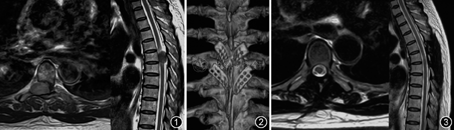

术前后常规CT、MRI检查(图1)。由影像专业医师测量患者术前后CT扫描中相应椎体中位线平面的矢状径,其结果统计学分析,P<0.05。术前确定手术区域脊柱情况及开放范围,术后比较脊柱形态有无变化。

15例肿瘤全部切除,术前症状明显改善或消失,切口7~9 d拆线,Ⅰ/甲愈合,无脑脊液漏发生。无肿胀、渗出等局部性及不明发热等全身性排异反应。随访3个月~2年,患者均无牵张、挛缩、异物感等主观不适反应,脊柱容量与外形饱满、无塌陷及移位,椎板–棘突获得骨性愈合,无骨质吸收表现,与复查CT及MRI检查结果一致(图2,图3)。术前后手术区域椎管腔前后径比较差异无统计学意义,t=–1.370,P>0.05,推定术后无继发椎管狭窄。